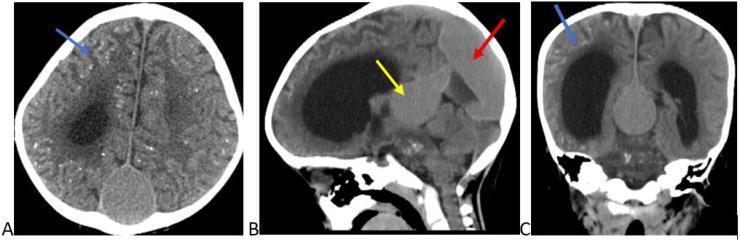

Diffuse bilateral cerebral calcification caused by Vein of Galen aneurysmal malformation in a two-year-old child: A rare presentation.

Intracranial calcification in pediatric patients below the age of 6 years is almost always pathologic. There are several causes of intracranial calcification, including congenital intracranial arteriovenous malformations, congenital infections, and neoplasms. Vein of Galen aneurysmal malformation is the most common of the congenital intracranial arteriovenous malformations. An untreated vein of Galen aneurysmal malformation causes chronic venous ischemia, leading to parenchymal dystrophic calcification. Here we report a case of a 2-year-old male child with developmental delay, seizure, hydrocephalus, and bilateral diffuse cerebral dystrophic calcification. In conclusion, in an appropriate clinical setting, although very rare, a vein of Galen aneurysmal malformation should be considered in the differential diagnosis of diffuse intracranial calcification, especially after ruling out TORCH infections.